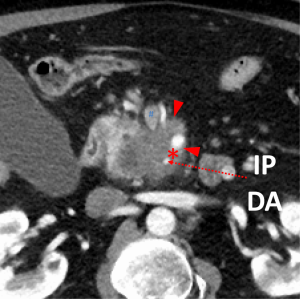

The first and most critical step in the management of PC is the determination of the clinical stage of disease and establishment of a histologic diagnosis. All disease-specific and stage-specific treatment planning is predicated on this step. With PC, it is critically important to use standardized, objective radiologic criteria for clinical staging. Modern imaging techniques have revolutionized the clinical staging of PC. Before the development of multidetector CT, up to 30% of patients with presumed resectable PC were found, at the time of operation, to have either metastatic disease or local tumor-associated vascular invasion which precluded resection (28). Currently, precise and objective anatomic radiographic criteria are used to determine the extent of the tumor-vascular relationship and to categorize clinical staging (Table 3). PC can be broadly divided into patients with inoperable disease (metastatic or locally advanced) and operable disease [borderline resectable (BLR) or resectable]. The majority of patients will present with metastatic disease, as evidenced by ascites/peritoneal implants, liver, or lung metastases. In the absence of metastatic disease, the clinical stage is determined by the relationship of the primary tumor to adjacent vasculature. As a general rule, any tumor abutment (≤180 degree tumor-vessel interface) or encasement (>180 degree) of the celiac axis, common hepatic artery, or SMA should be considered a contraindication to immediate surgery. A patient is deemed to have locally advanced, unresectable disease when: (I) the tumor encases the SMA or celiac axis, as defined by >180 degrees of the circumference of the vessel; or (II) there is occlusion of the SMPV confluence without the possibility for venous reconstruction (Figure 1). Patients who have tumor abutment, without encasement, of the SMA or celiac axis, or short segment encasement of the hepatic artery are considered to have BLR PC (Figure 2) (29). In addition, patients with tumors that cause >50% narrowing or short segment occlusion of the SMV/PV that may be amenable to reconstruction are also considered to be BLR. There is emerging consensus that even more subtle tumor-vein abutment may be best considered BLR, especially with respect to the use of neoadjuvant therapy rather than surgery-first (30). Finally, patients who have radiographic lesions which are indeterminate for metastases (usually too small to accurately characterize), even in the absence of SMA abutment or venous narrowing, are also considered by some institutions to have BLR PC (31). Radiographic findings of a resectable PC are (I) the absence of tumor-arterial abutment or encasement; and (II) <50% narrowing of the SMV/PV (Figure 3).